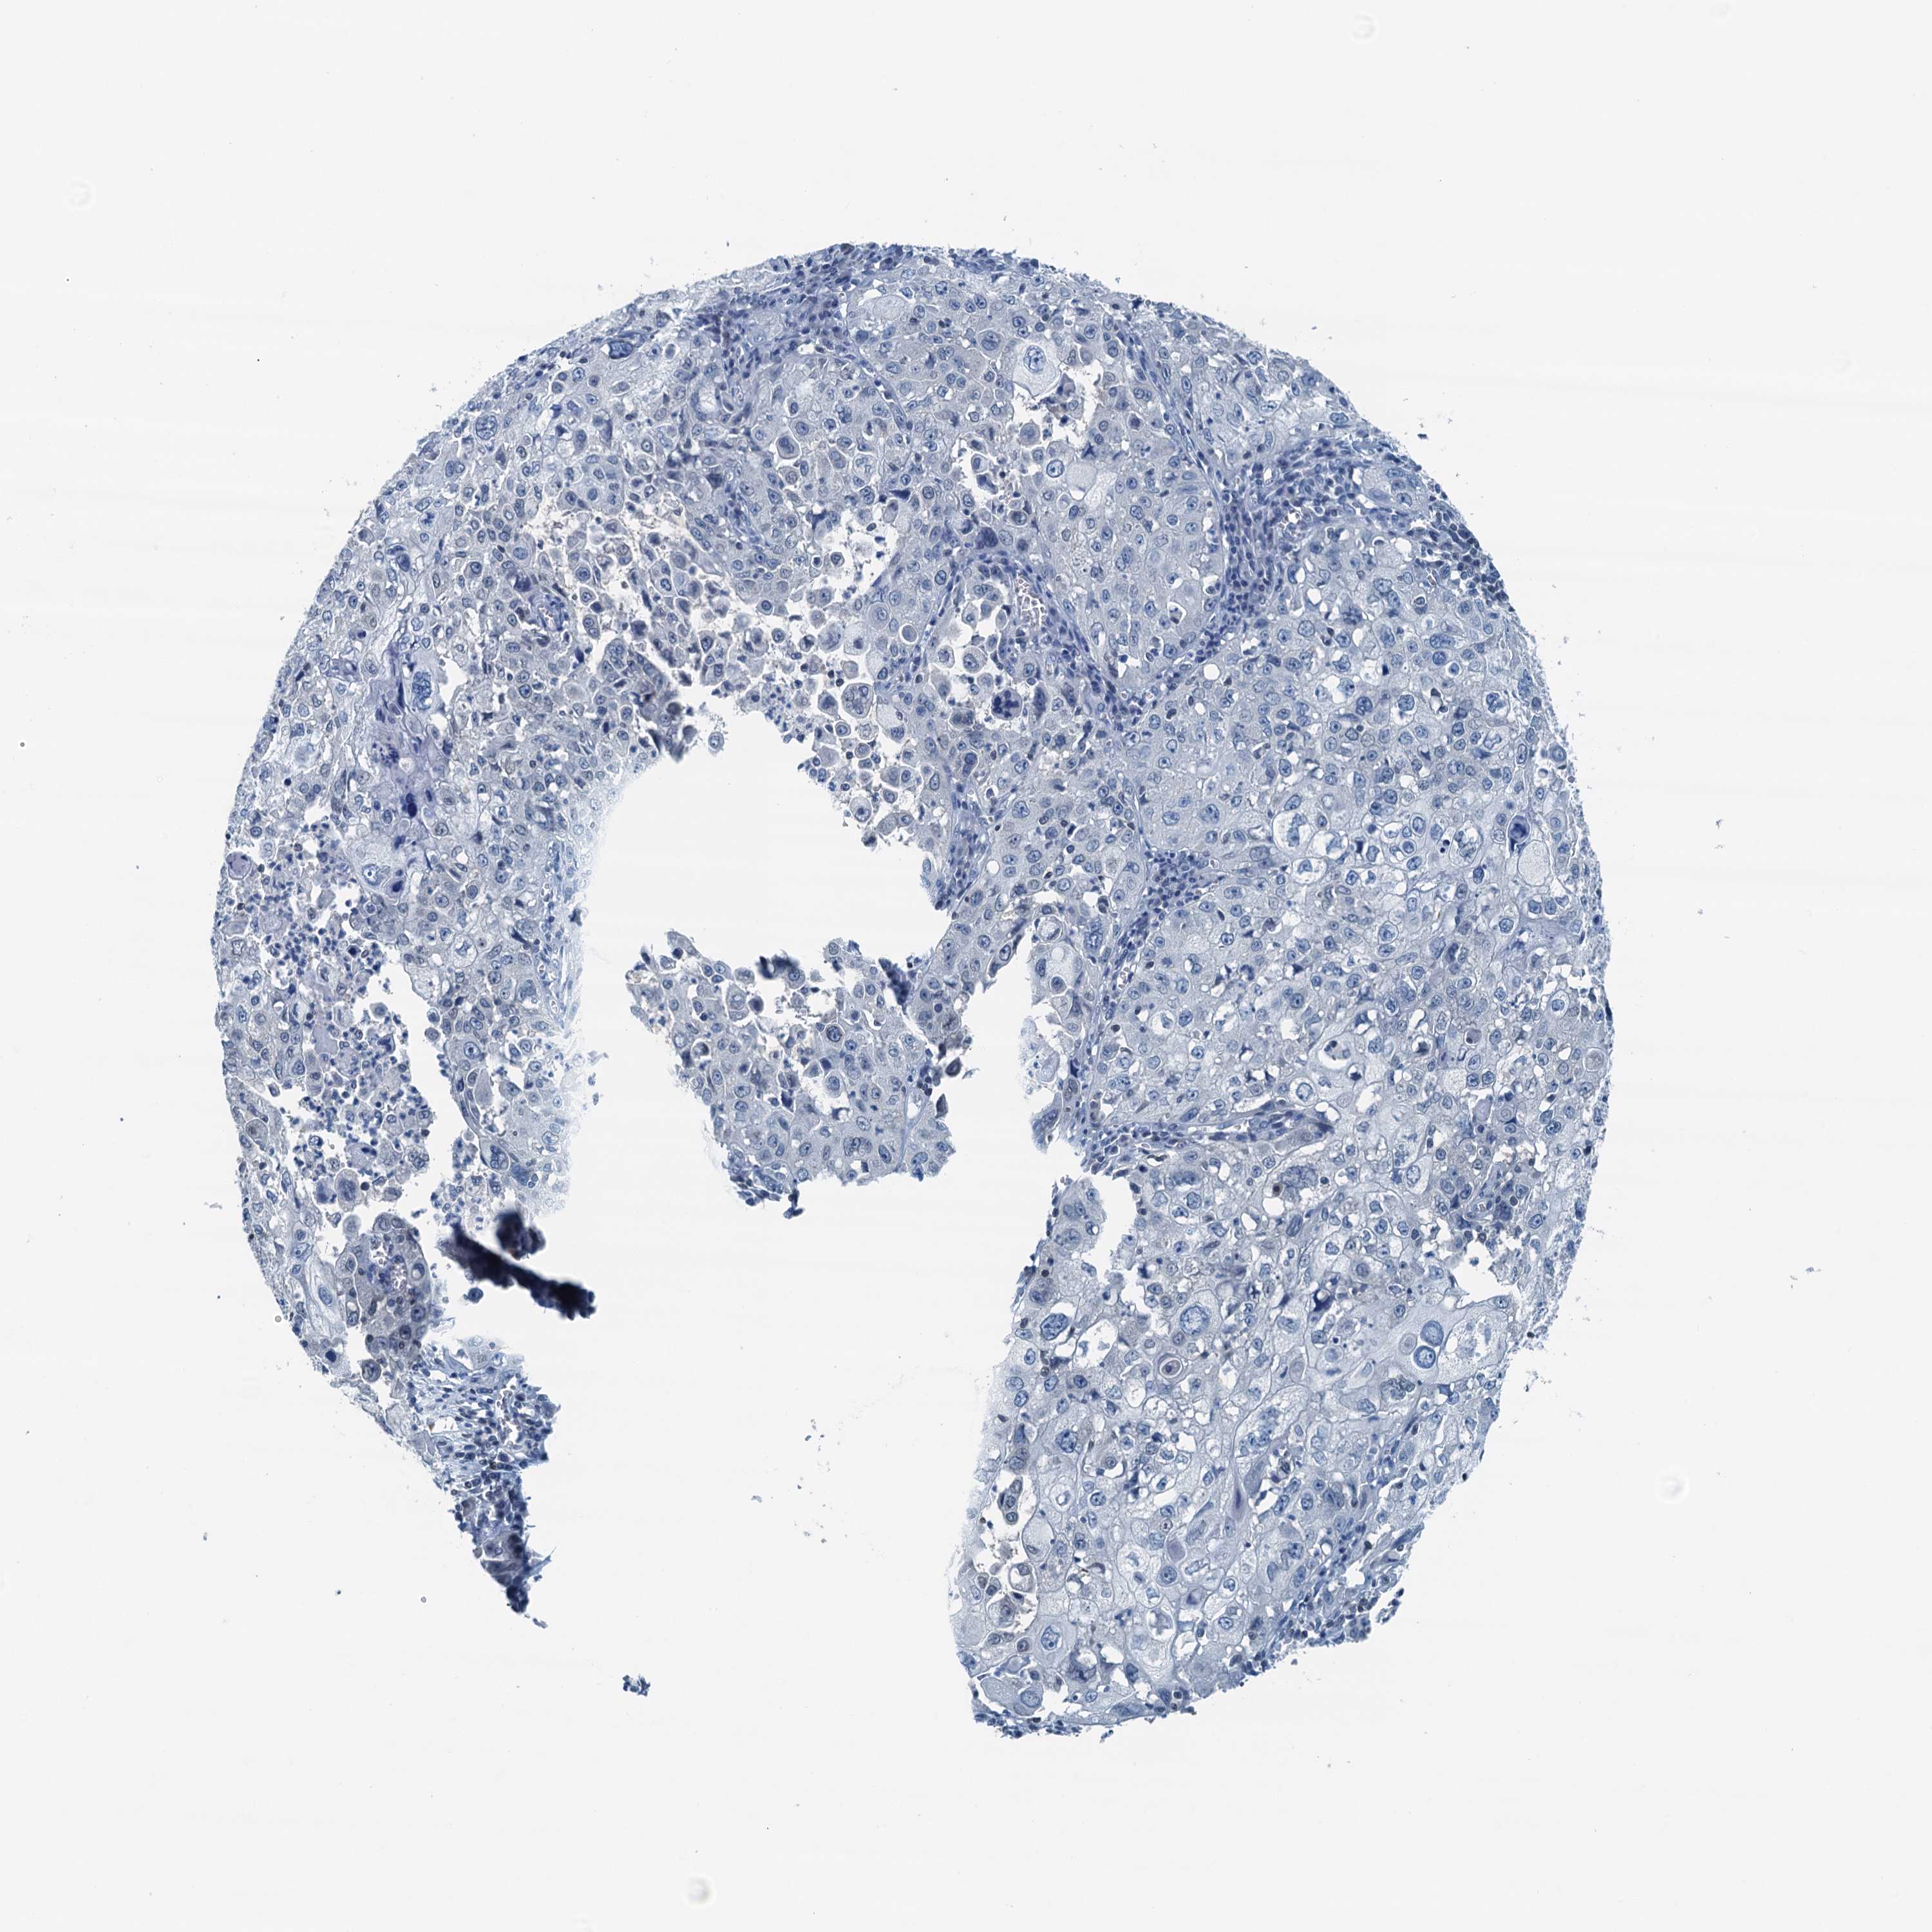

CERVICAL CANCER - Protein expressioni

A mouse-over function shows sample information and annotation data. Click on an image to view it in a full screen mode. Samples can be filtered based on level of antibody staining by selecting one or several of the following categories: high, medium, low and not detected. The assay and annotation is described here.

Note that samples used for immunohistochemistry by the Human Protein Atlas do not correspond to samples in the TCGA dataset.

Antibody stainingi

Antibody staining in the annotated cell types in the current human tissue is reported as not detected, low, medium, or high, based on conventional immunohistochemistry profiling in selected tissues. This score is based on the combination of the staining intensity and fraction of stained cells.

Each image is clickable and will lead to virtual microscopy that enables deeper exploration of all samples and also displays staining intensity scores, fraction scores and subcellular localization as well as patient and tissue information for each sample.

Antibody HPA040511

Staining

High

Medium

Low

Not detected

Intensity

Strong

Moderate

Weak

Negative

Quantity

>75%

75%-25%

<25%

None

Location

Nuclear

Cytoplasmic/membranous

Cytoplasmic/membranous,nuclear

Squamous cell carcinoma, NOS

Adenocarcinoma, NOS